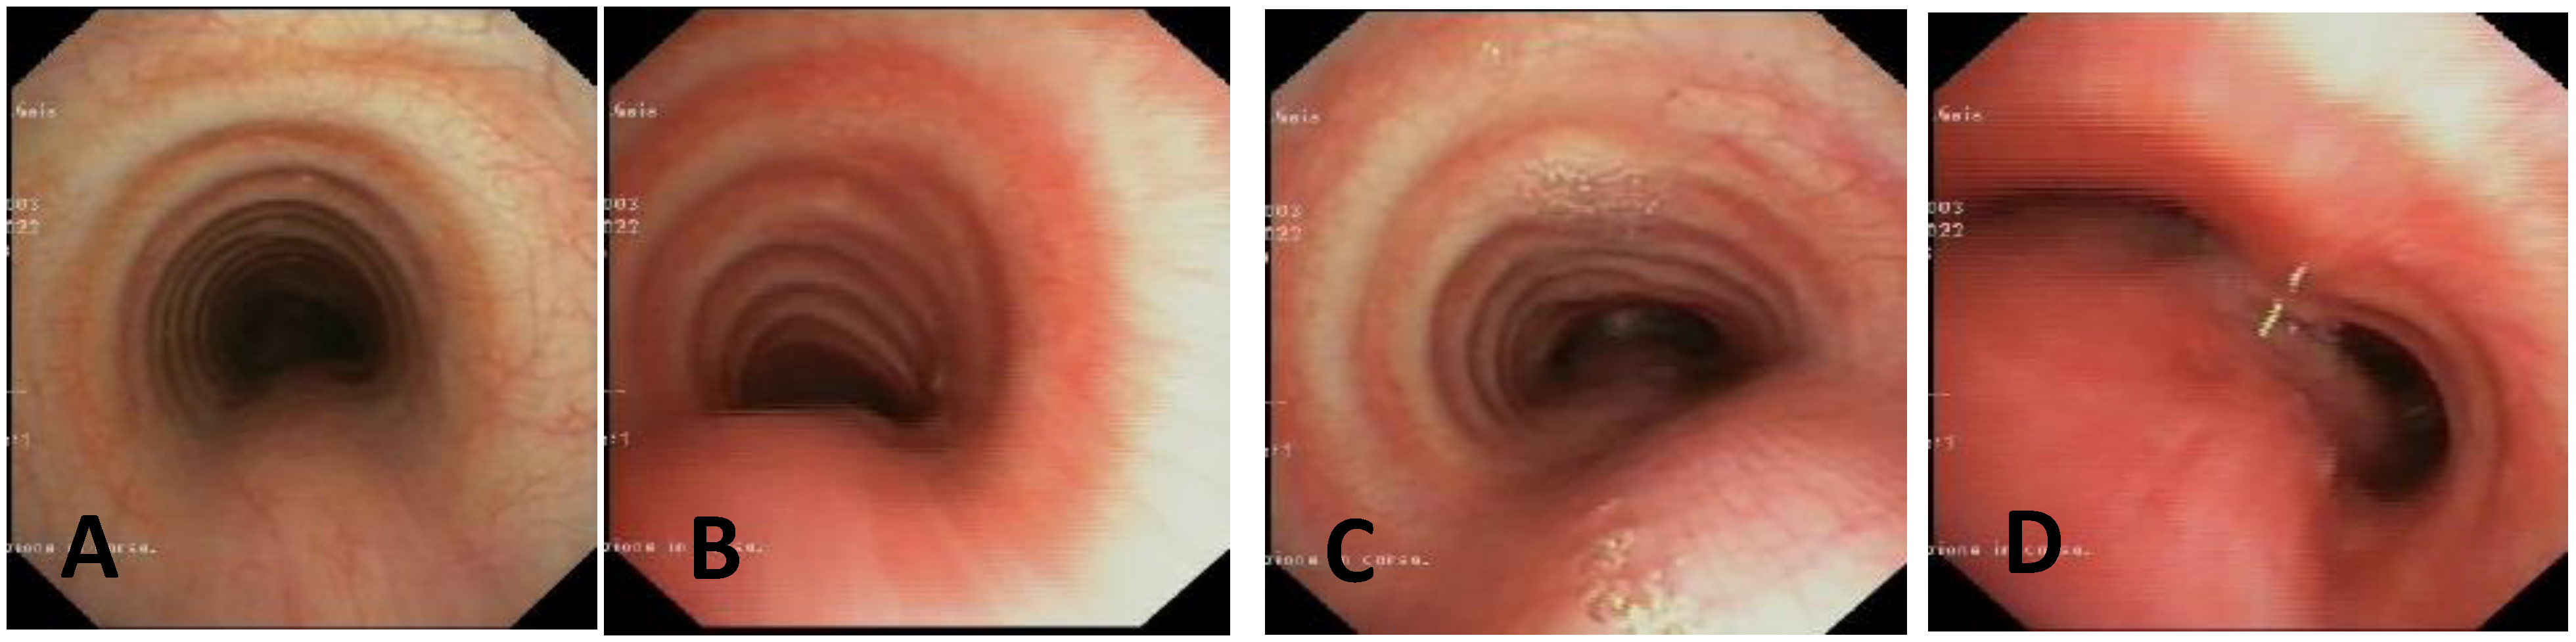

- Static VBS (SVBS) is the phase in which the tracheal lumen is evaluated during spontaneous, quiet breathing, but there should also be a phase of:

- Dynamic VBS (DVBS), in which the patient (while sedation, as it is at the end of the examination, becomes increasingly superficial), is stimulated to cough by contact of the endoscope with the carina and/or main bronchial walls. The patient, performing abdominal straining to attempt to cough, increases the intrathoracic pressure similarly to what happens when the patient is awake. The increasing pressure, if there is malacia/extrinsic compression or hypermobility of the pars membranacea, causes a pathological (i.e., greater than 50%) decrease in tracheal lumen, as can happen in everyday life [27,28].

| Score: 0 | Pulsating extrinsic deformation on the anterior tracheal wall, reduction in the APD of the trachea of less than 50% compared to the suprastenotic tract, even during expiration. Good representation of the cartilaginous rings. Figure 9, score 0 |

| Score: 1 | Reduction in the tracheal APD between 50% and 75% compared to the suprastenotic tract, with an absence of contact between the anterior tracheal walls and the pars membranacea, even when the patient performs abdominal straining. Good representation of the cartilaginous rings. Figure 9, Score 1 |

| Score: 2 | Reduction in the APD of the trachea between 75% and 90% compared to the suprastenotic tract and/or anterior tracheal wall and pars membranacea, tending to touch, without complete closure of the lumen, even when the patient performs abdominal straining, with poor representation of the cartilaginous rings. Figure 1, score 2 |

| Score: 3 | Reduction in the APD of the trachea is already greater than 90% during the expiratory phase, when the tracheal lumen completely closes. Figure 9, score 3 |